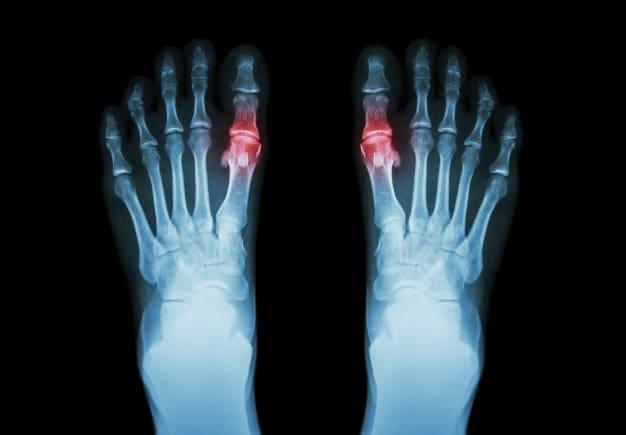

داء الملوك (Gout) أو ما يعرف بالنقرس، هو أحد أنواع التهاب المفاصل (Arthritis) الشائعة الحدوث، الذي عادةً ما يحدث فجأةً في أصبع القدم الكبير مسببًا الام شديدة، من الممكن أن يصيب داء الملوك مفاصل أخرى و يؤثر في المناطق المحيطة بها، مثل الكاحل، الركبة، والقدم.

- الالتهاب والاحمرار: حيث تصبح المفاصل المصابة متورمة، حساسة، دافئة، ومحمرة.

- التصوير بالأشعة السينية.